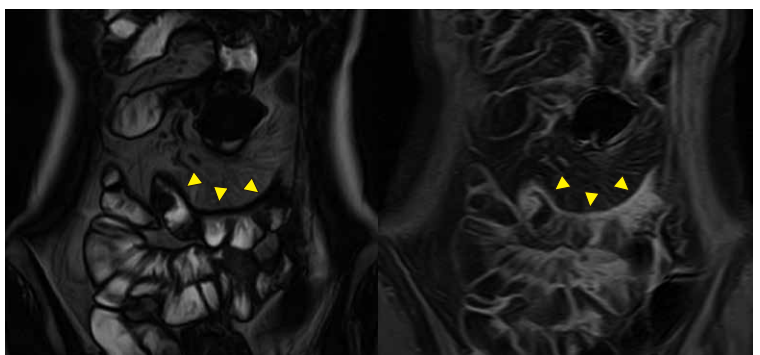

MRエンテログラフィー 1

縦走潰瘍。弧状変形を伴い、腸間膜の脈管は増強されcomb signを呈している。造影では縦走潰瘍部が増強されている。

出典

img

1: 難治性炎症性腸管障害に関する調査研究(久松班):一目でわかるIBD 炎症性腸疾患を診察されている先生方へ(第四版) 「令和4年度において、厚生労働科学研究費補助(難治性疾患等政策研究事業(難治性疾患政策研究事業)を受け、実施した研究の成果」、2023年、P30